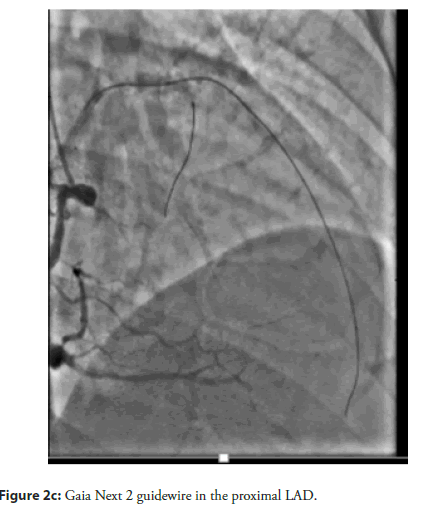

The patient and his family declined Coronary Artery Bypass Graft (CABG) surgery; therefore, the primary treatment strategy was to attempt revascularization of the LAD CTO lesion. An antegrade approach was selected, with the right femoral artery used as the primary access route and the right radial artery used for additional support. The initial attempts were made using Fielder XT, Fielder XT-R, and Gaia Next 2 guide wires (Figure 2a–Figure 2c). However, the Caravel microcatheter could not be advanced across the tight lesion. Therefore, predilatation was attempted using a 1.25 × 10 mm balloon followed by a 2 × 12 mm Non-Compliant (NC) balloon. Unfortunately, the wire was found to be in a false tract, which resulted in a Type III LAD perforation with subsequent cardiac tamponade. Emergency pericardiocentesis was performed (Figure 3a, Figure 3b). The LAD perforation was successfully sealed using 2 mm and 3 mm Hilal coils (Figure 4a–Figure 4c).